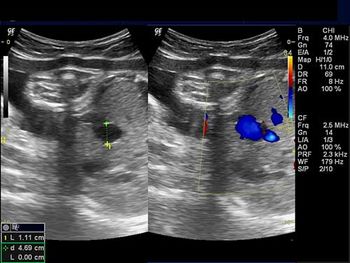

This 18-week fetus has a vascular anomaly. Can you identify it?